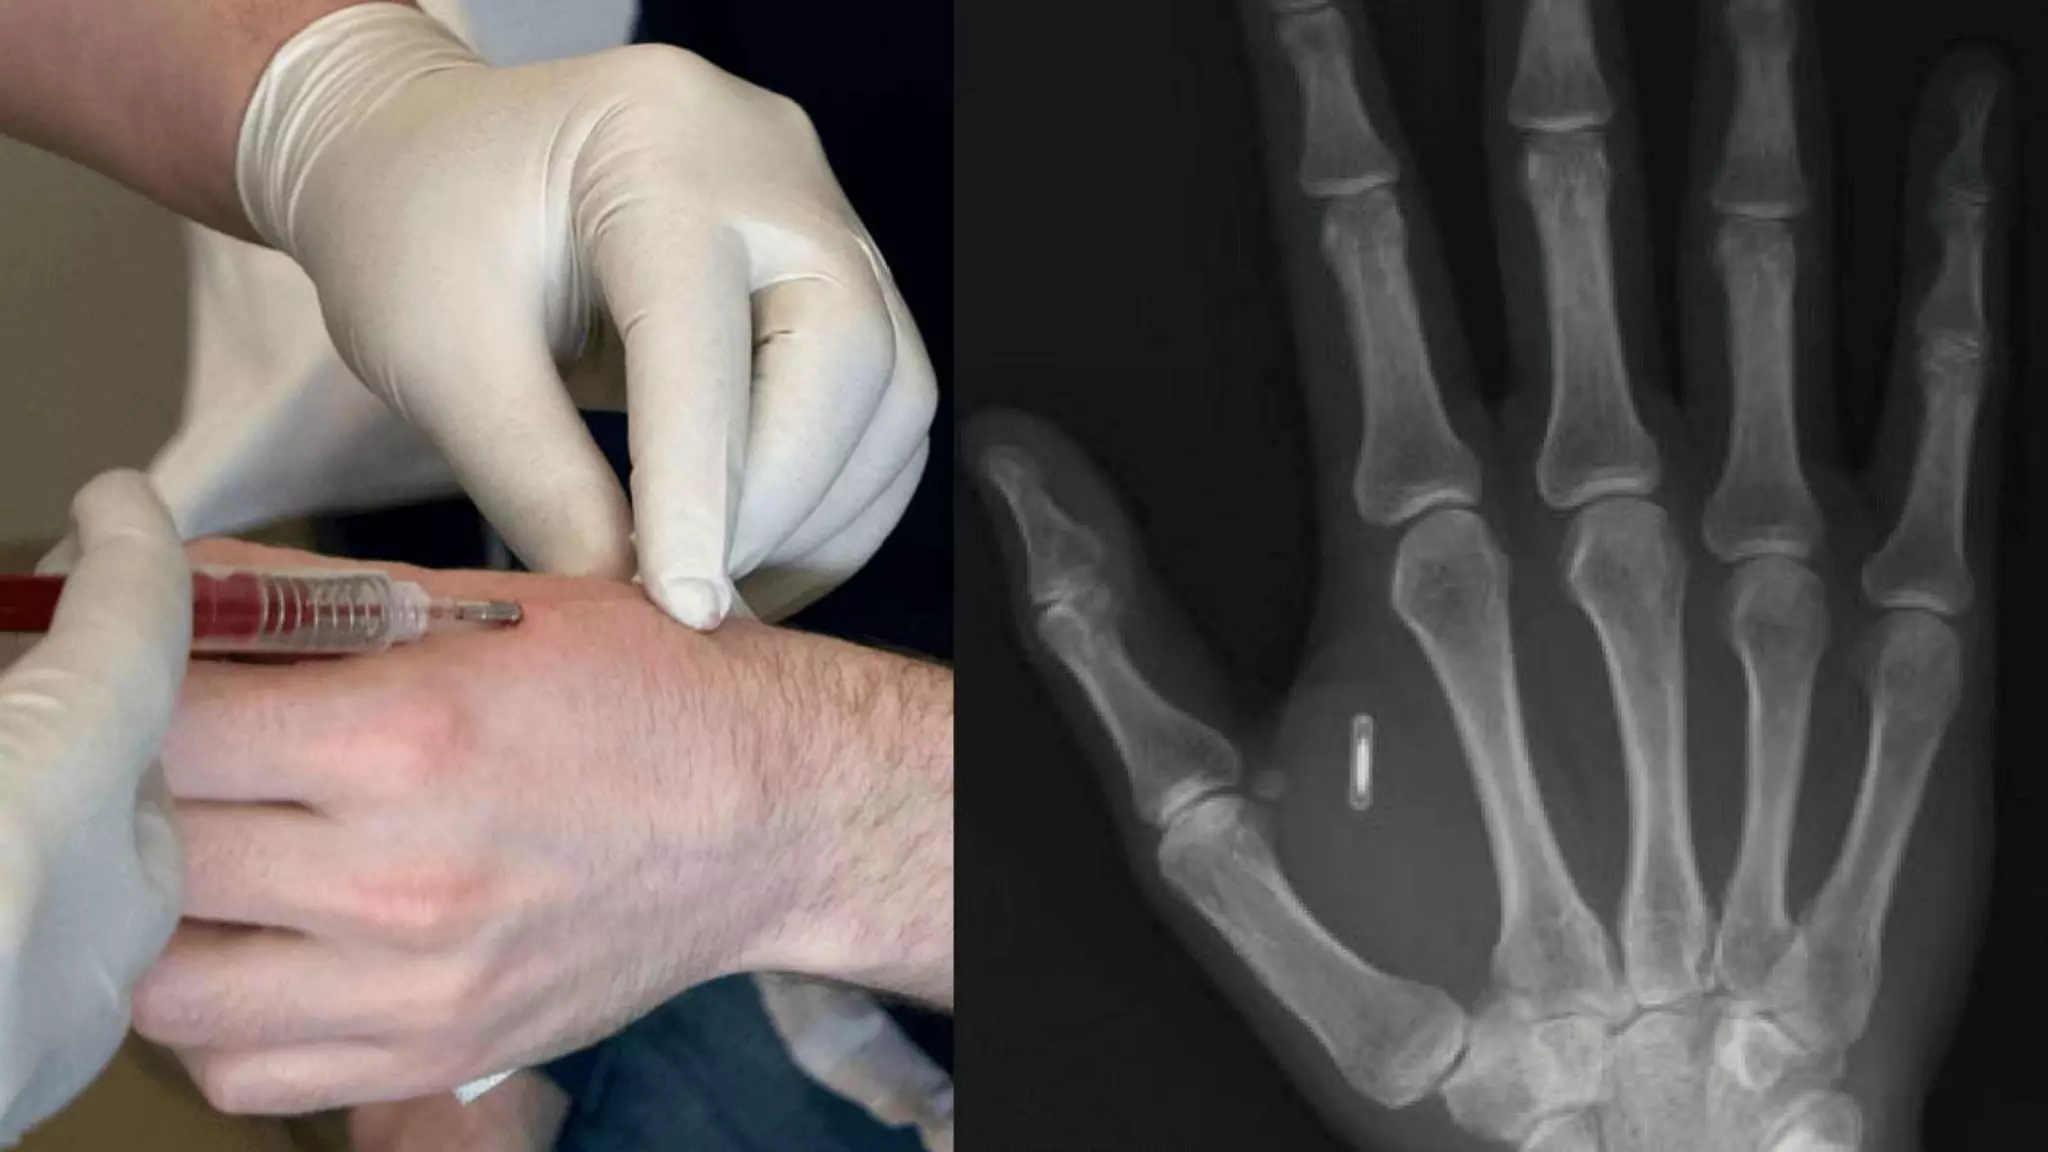

Technik im Körper: Implantate

Belegschaften chippen:

Bequem und fragwürdig

Schwedische Chip-Pionier:innen

• Jowan Österlund von Biohax bietet die Chips an, setzt sie

bei Chipping-Parties auch ein

• Das Startup-Center Epicenter bietet Chips an um Zugang

zum Gebäude, Bezahlen von Erfrischungen am Automaten

etwa zu erleichtern: Bequemlichkeit

• Problematisch weil Menschen trackbar sind, auch wenn

der Chip „passiv“ ist und selbst keine Informationen lesen

“The human chips are

sold by a Swedish

company called Biohax

International, founded

by Jowan Österlund,

who said he was

inspired by 1995 movie

Johnny Mnemonic, in

which Keanu Reeves

plays a man who stores

sensitive data in an

implant.”